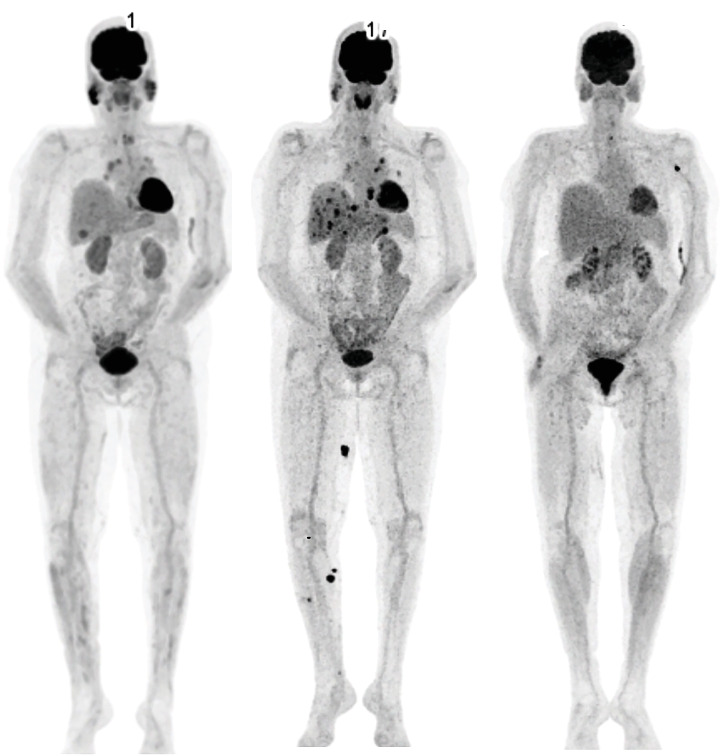

恶性肿瘤高钙血症是一种众所周知的癌症患者现象,往往与预后不良有关。免疫检查点抑制剂的发现通过改善许多不同癌症类型的预后,彻底改变了癌症治疗。不幸的是,免疫相关的不良事件经常发生,特别是双检查点抑制。我们提出一个病例严重高钙血症在一个65岁的妇女接受治疗转移性恶性黑色素瘤。在开始使用ipilimumab-nivolumab 11周后,患者出现严重的高钙血症,同时伴有炎症和肝炎。鉴于临床检查、影像学表现和实验室值可能与进行性疾病相一致,最初推测这是由于恶性肿瘤的高钙血症。高钙血症对双膦酸盐、静脉生理盐水和甲基强的松龙反应良好。有趣的是,出院后不久进行的氟脱氧葡萄糖-正电子发射断层扫描/计算机断层扫描(FDG-PET/CT)显示代谢完全缓解,因此不太可能出现恶性高钙血症。回顾病史、影像学和实验室检查,发现几个与结节样反应相符的特征。我们假设该反应导致1- α羟化酶升高,从而促进骨化三醇介导的高钙血症。在这篇报告中,我们总结了以前发表的关于免疫检查点抑制剂诱导的高钙血症的病例报告,并讨论了在这种罕见的免疫相关不良事件中引起高钙血症的各种机制。免疫检查点抑制剂可以诱导甲状旁腺激素相关蛋白(PTHrP)、骨化三醇的产生,并可能导致低皮质醇血症,所有这些都可以破坏钙稳态。通过这个病例,我们提供了越来越多的证据,证明高钙血症是一种免疫相关的不良事件,并旨在提高临床医生对这种潜在并发症的认识。早期识别对这种危及生命的疾病至关重要,因为它对常规治疗是难治性的,可能需要皮质类固醇治疗。

Hypercalcemia of malignancy is a well-known phenomenon in cancer patients, often associated with poor prognosis. The discovery of immune checkpoint inhibitors has revolutionised cancer therapy by improving prognosis in numerous different cancer types. Unfortunately, immune-related adverse events frequently arise, particularly with dual checkpoint inhibition. We present a case of severe hypercalcemia in a 65-year-old woman undergoing treatment for metastasised malignant melanoma. Eleven weeks after initiating ipilimumab-nivolumab, the patient developed severe hypercalcemia, along with inflammation and hepatitis. This was initially presumed to be due to hypercalcemia of malignancy, given the clinical examination, imaging findings and laboratory values potentially consistent with progressive disease. The hypercalcemia responded well to bisphosphonates, intravenous saline and methylprednisolone. Interestingly, fluorodeoxyglucose-positron emission tomography/computed tomography (FDG-PET/CT) performed shortly after hospital discharge showed a complete metabolic remission, thereby making hypercalcemia of malignancy unlikely. Review of her medical history, imaging and laboratory revealed several features consistent with a sarcoid-like reaction. We hypothesise that this reaction led to elevated 1-alpha hydroxylase, thereby facilitating calcitriol-mediated hypercalcemia. In this report, we summarise previously published case reports on immune checkpoint inhibitor-induced hypercalcemia and discuss the various mechanisms that cause hypercalcemia in this rare immune-related adverse event. Immune checkpoint inhibitors can induce production of parathyroid hormone-related protein (PTHrP), calcitriol, and may cause hypocortisolaemia, all of which can disrupt calcium homeostasis. Through this case, we contribute to the growing body of evidence regarding hypercalcemia as an immune-related adverse event and aim to raise awareness among clinicians of this potential complication. Early recognition is critical for this life-threatening condition, as it can be refractory to conventional therapies and may necessitate corticosteroid therapy.